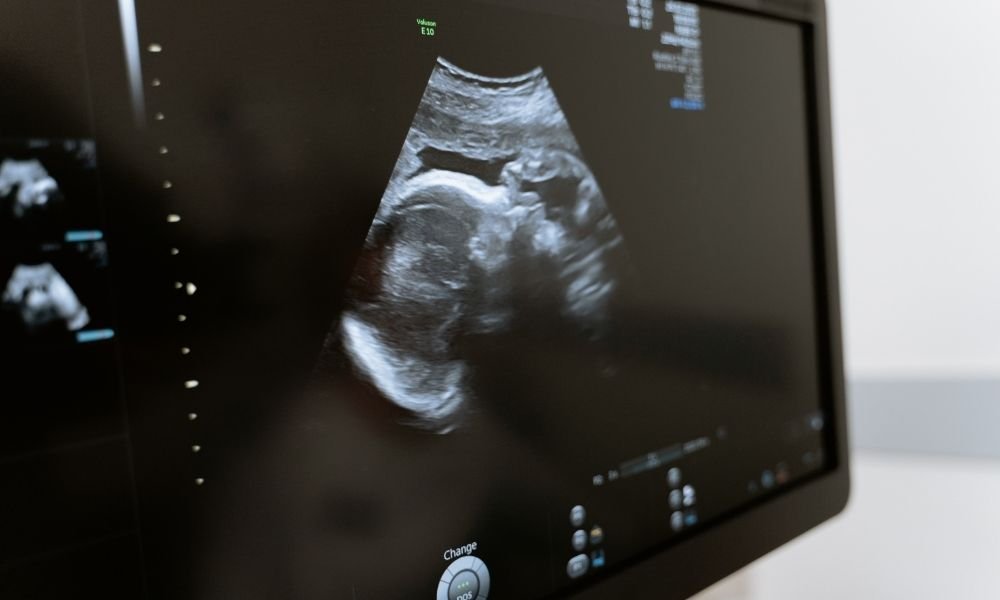

4 Boyutlu Ultrason Nedir? 4 boyutlu ultrason, gebelik sürecinde anne karnındaki bebeğin hareketli ve ayrıntılı görüntülerini sağlayan ileri bir görüntüleme…